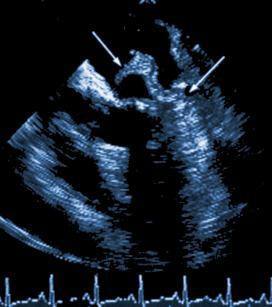

En el endocardio, generalmente en las válvulas, se forma una vegetación o verruga que es una masa donde anidan los microorganismos. Desde la vegetación los gérmenes invaden constantemente la sangre produciendo una bacteriemia persistente.

- Ecocardiograma: Demuestra la vegetación.

- Ecocardiograma positivos.